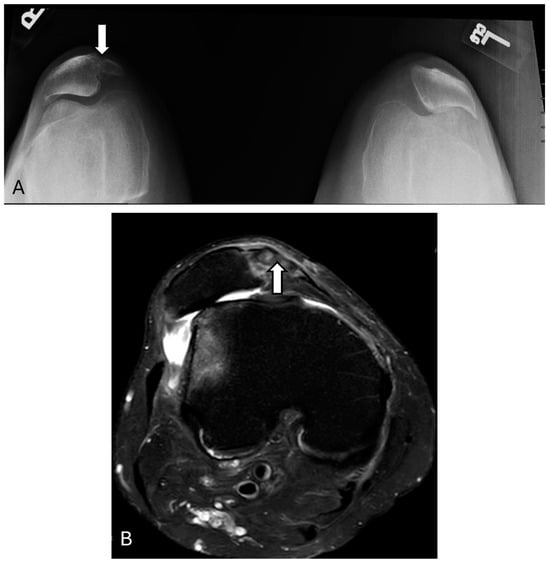

3.8. Prepatellar Bursitis